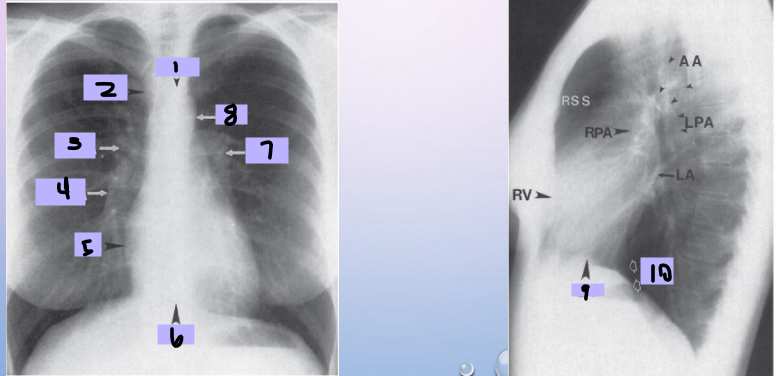

Aortic arch

#1

Superior vena cava

#2

Right pulmonary artery

#3

Right descending pulmonary artery

#4

Right atrium

#5

Right ventricle

#6

Left pulmonary artery

#7

Descending aorta

#8

Left ventricle

#9

Inferior vena cava

#10